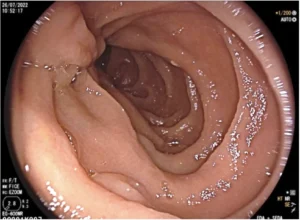

A su segundo día de hospitalización, se realiza endoscopia digestiva alta que reporta mucosa gástrica eritematosa en toda su extensión con algunas erosiones planas de aspecto nodular en cuerpo gástrico, sin sitios de sangrado activo hasta segunda porción de duodeno. (imagen 1). Se reporta aumento de temperatura de 38.3ºC, por lo que se solicita PCR, EMO más urocultivo y prueba de Sarscov2 la cual resulta negativa.

Imagen 1. Exploración endoscópica